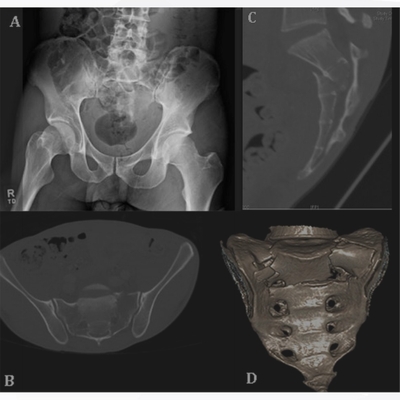

Click on an image below to view more info.